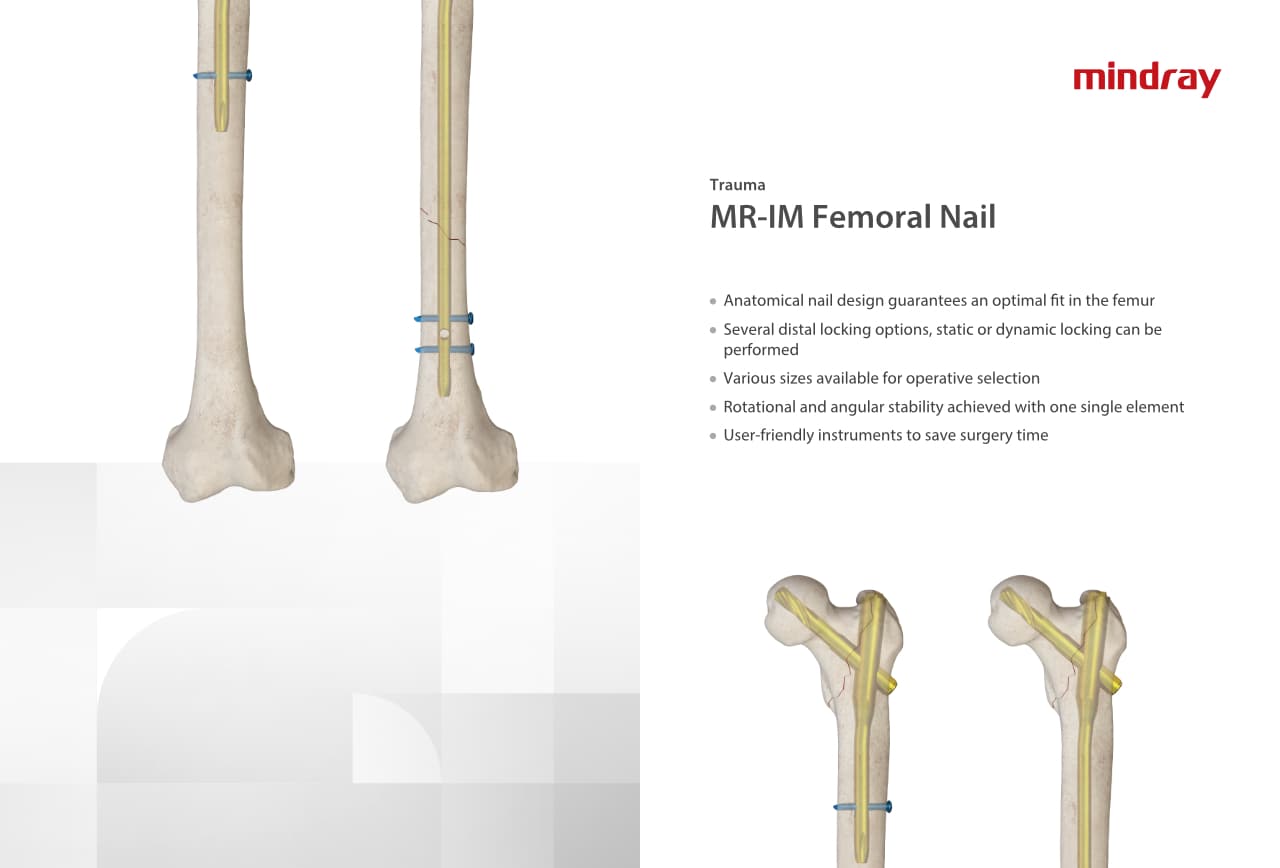

Traumatologie